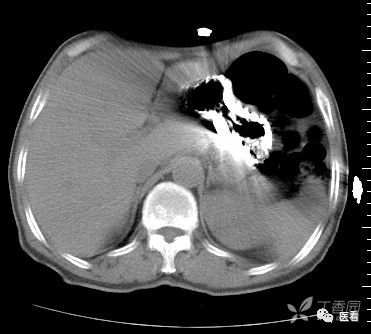

CT造影中可能出现的假象——涡流

这里强调一个CT造影中可能产生的假象——涡流

也就是团注(高压注射器快速注入)的碘对比剂与血液没有混匀之前,没有对比剂的血液呈低密度(红箭头),有对比剂的血流呈高密度,不要误认为是血栓